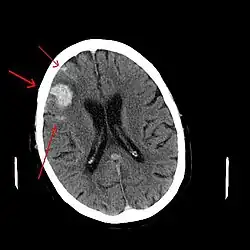

CT scan van een spontaan intracerebraal hematoom | ||||

Intracerebraal hematoom is de medische aanduiding van een bloeding, waarbij het bloed zich in het hersenweefsel bevindt. Dit is de meest voorkomende hersenbloeding en deze treedt spontaan op. De gevolgen voor de patiënt zijn ongeveer hetzelfde als bij een herseninfarct. De belangrijkste oorzaak is hoge bloeddruk, dus hypertensie. Dit is de enige vorm die een echte 'hersenbloeding' mag heten.